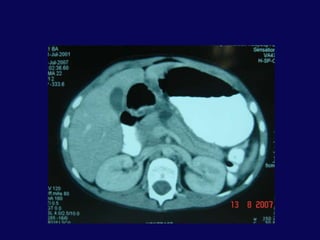

SK 6,E20 Gün önce bisikletten düşme dış merkezde taip batın distansiyonu gelişmesi üzerine İTF ne sevkFM: Distansiyon ve yaygın hassasiyet

BT: pankreas orta hatta laserasyon ve peripankreatik sıvı

SK 6,E